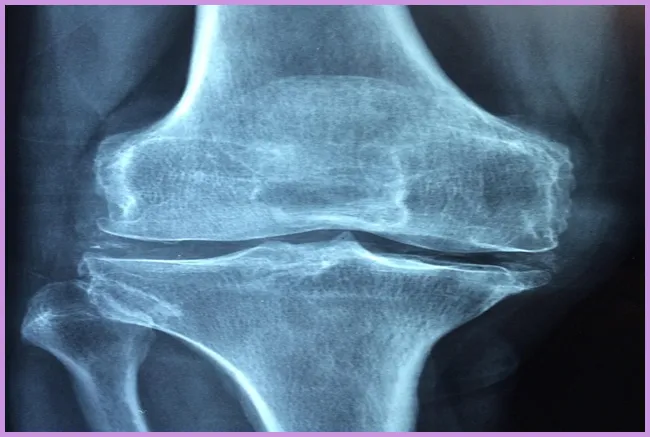

퇴행성 관절염의 원인과 증상

퇴행성 관절염은 주로 노화와 관련이 깊습니다. 나이가 들면서 관절의 유연성이 떨어지고, 연골이 줄어들어 통증을 느끼게 됩니다. 또한 비만, 과도한 운동, 유전적 요인 등이 퇴행성 관절염을 악화시킬 수 있습니다. 주요 증상으로는 관절의 경직, 통증, 불균형 등이 있습니다. 이런 증상을 경험할 때면 일상적인 활동도 어렵게 느껴지곤 하지요.